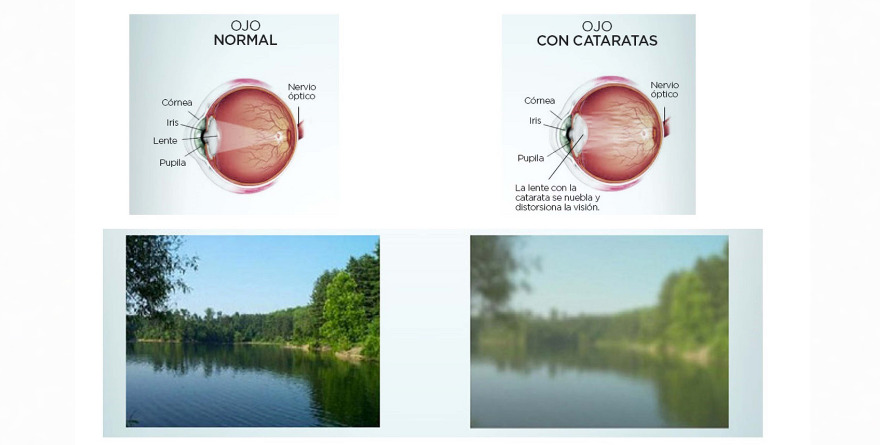

CATARATAS: MÁS FRECUENTES Y CADA VEZ MÁS TEMPRANAS

Las cataratas oculares van en aumento a nivel global por el envejecimiento de la población,…